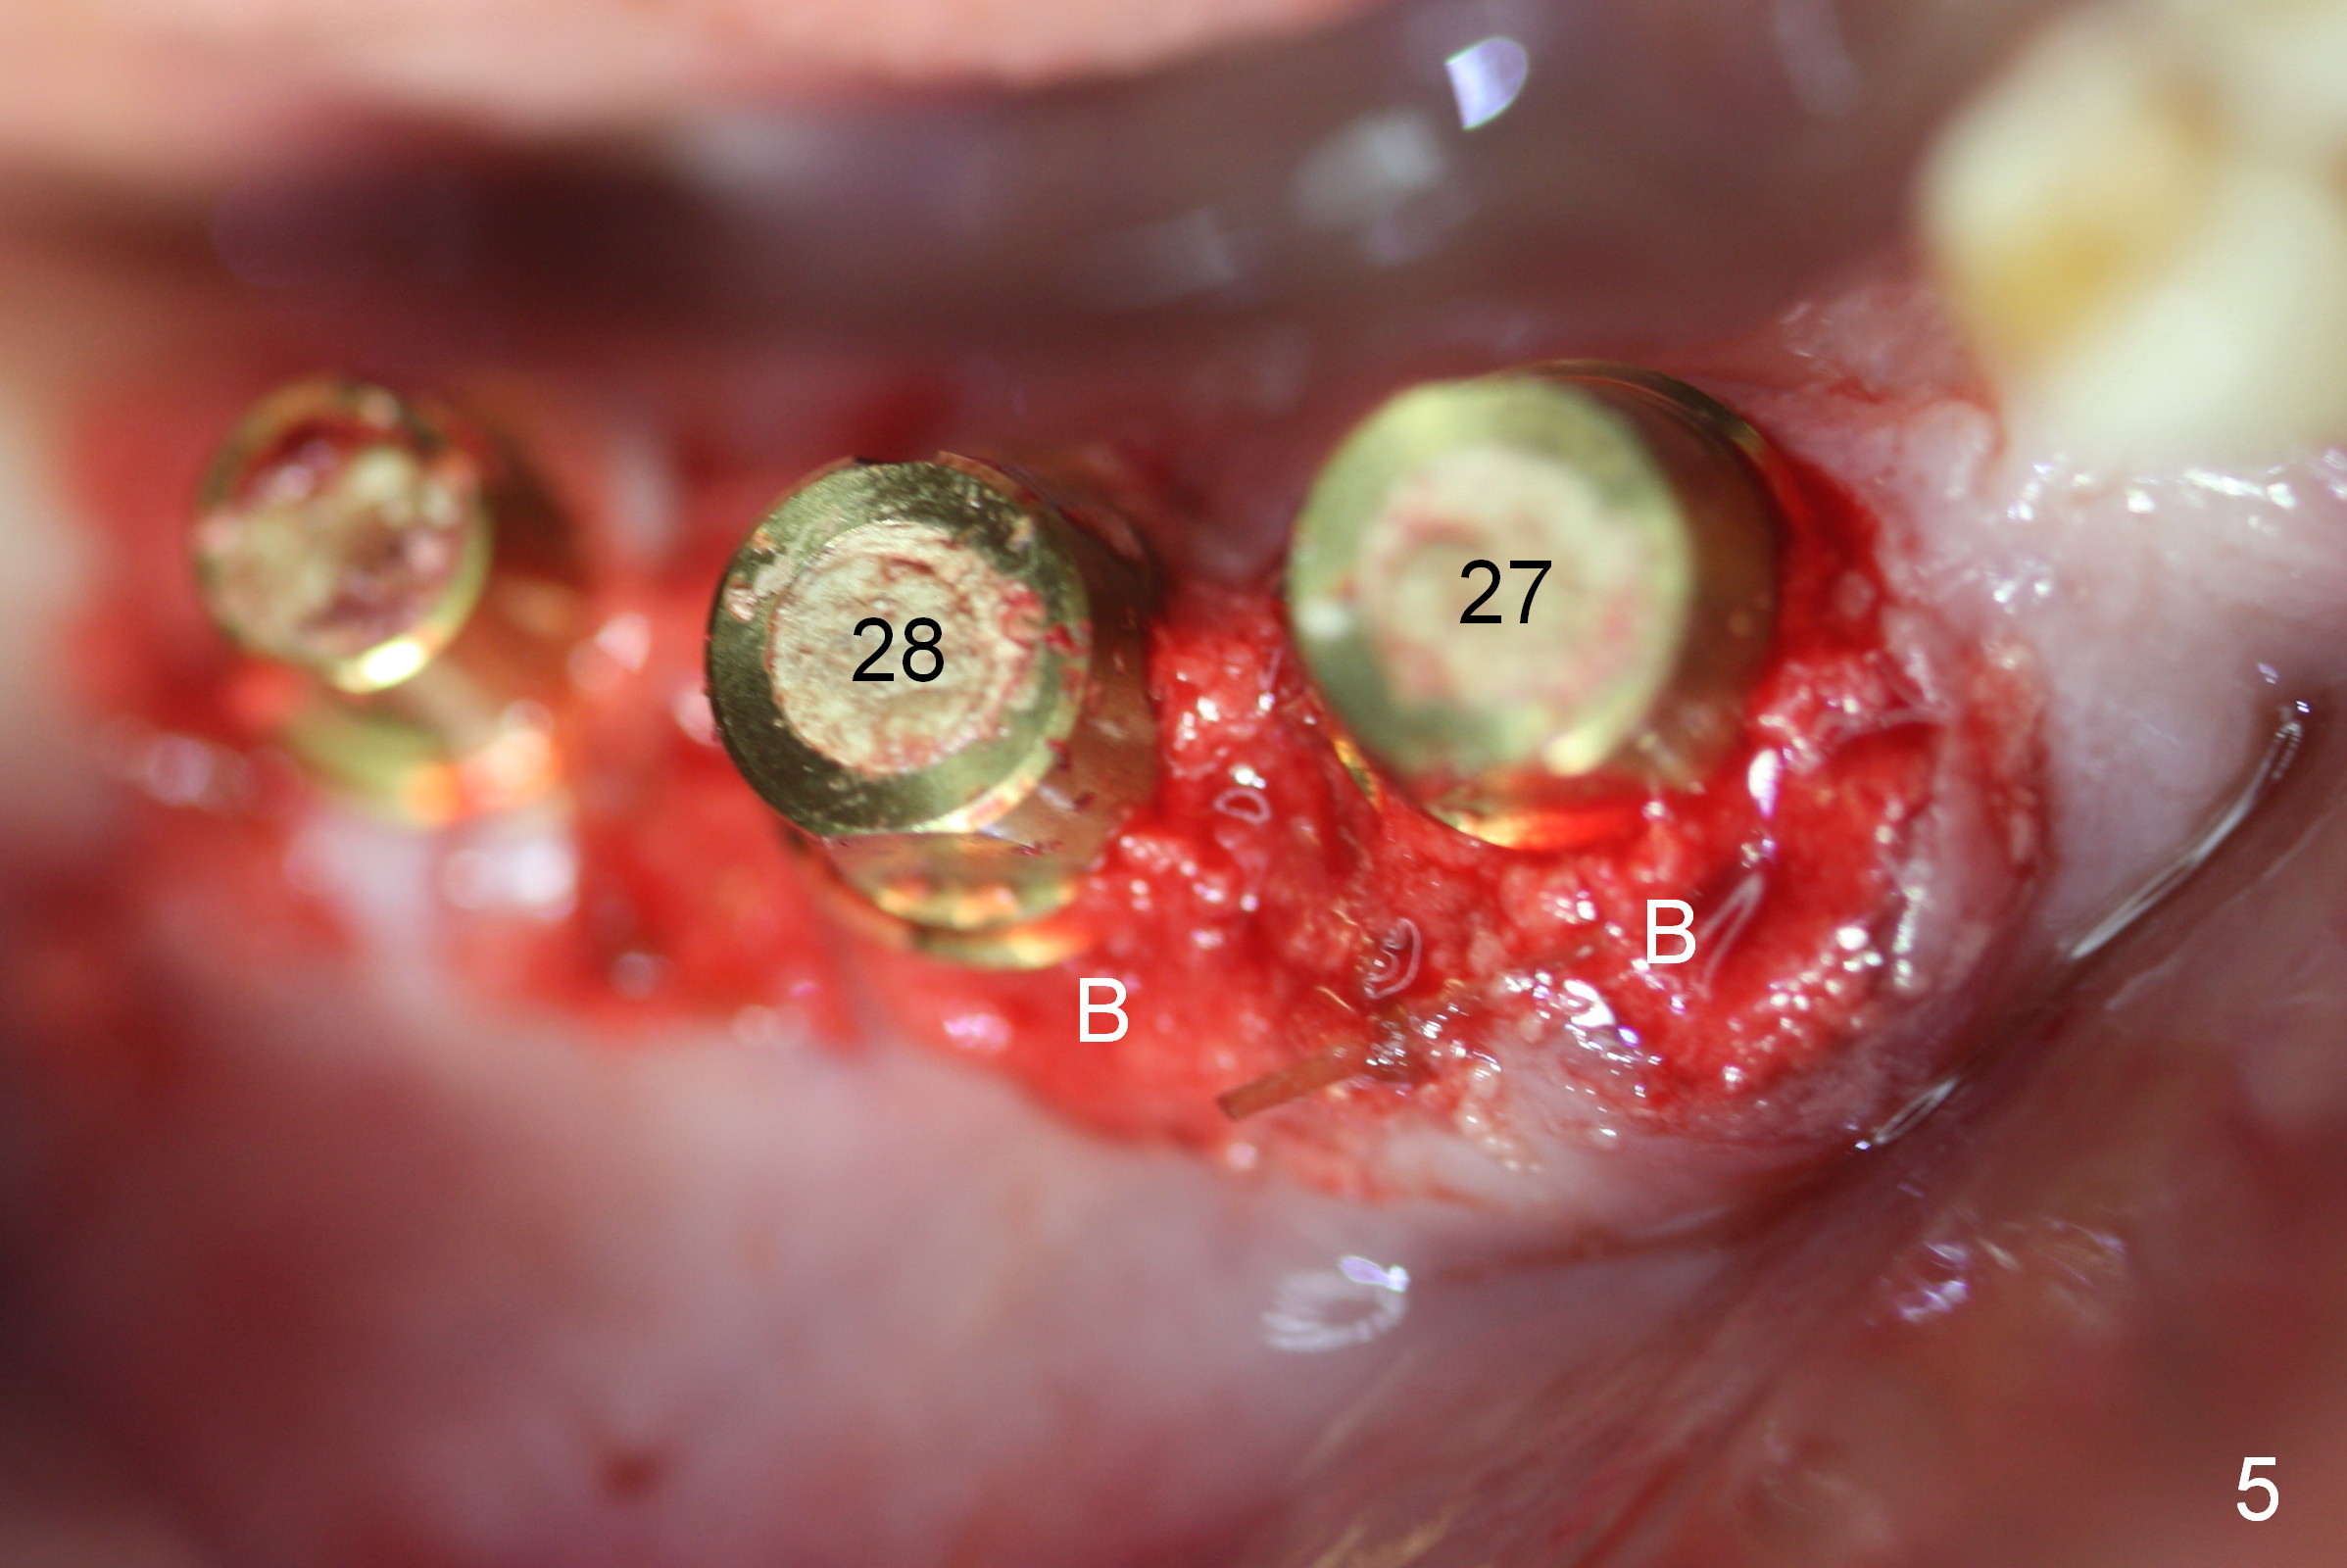

A 86-year-old man returns to office for the lower right quadrant reconstruction with implants. In addition to the immediate ones at the sites of #27 and 28 (Fig.1), how many and where else? The patient reveals that he does not plan to get an implant at the site of #3 (Fig.2). Therefore there is no need for an implant at #30. Preop CT shows that bone width is compromised at #26. So the 3rd site will be #29 (Fig.3,4). All of the 3 implants (4.5x14 mm, 4.5x12, and 4.1x12 mm) achieve primary stability (»55 Ncm). An immediate provisional could be provided, but it seems difficult to close the buccal (Fig.5 B) gaps of #27 and 28 after bone graft with the provisional. In contrast, the gingiva adapts to the implant at #29 well (Fig.6 B). Perio dressing is applied to the abutments (Fig. 7: #27-29), the edentulous space at #26 and the neighboring teeth (#23,24). It would be ideal to apply a non-resorbable membrane to the buccal opening at #27,28 (Fig.8 white line) prior to perio dressing placement. In case of dislodgement of the latter, the membrane is able to keep bone graft in place.